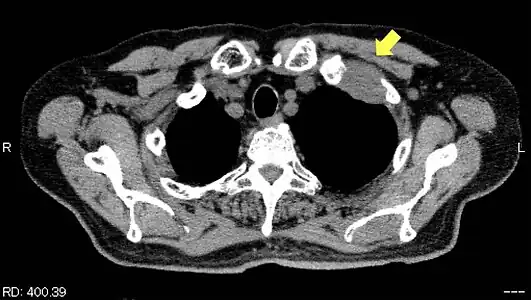

TDM d'une tumeur de Pancoast gauche envahissant l'arc antérieur de la 1re et de la 2e côte (flèche jaune).

PET-scanner du même patient[14].

Les côtes sont envahies de manière isolée chez 65 % des patients[15] ; seulement 8 % présentent un envahissement en bloc des côtes et des vertèbres adjacentes[15].